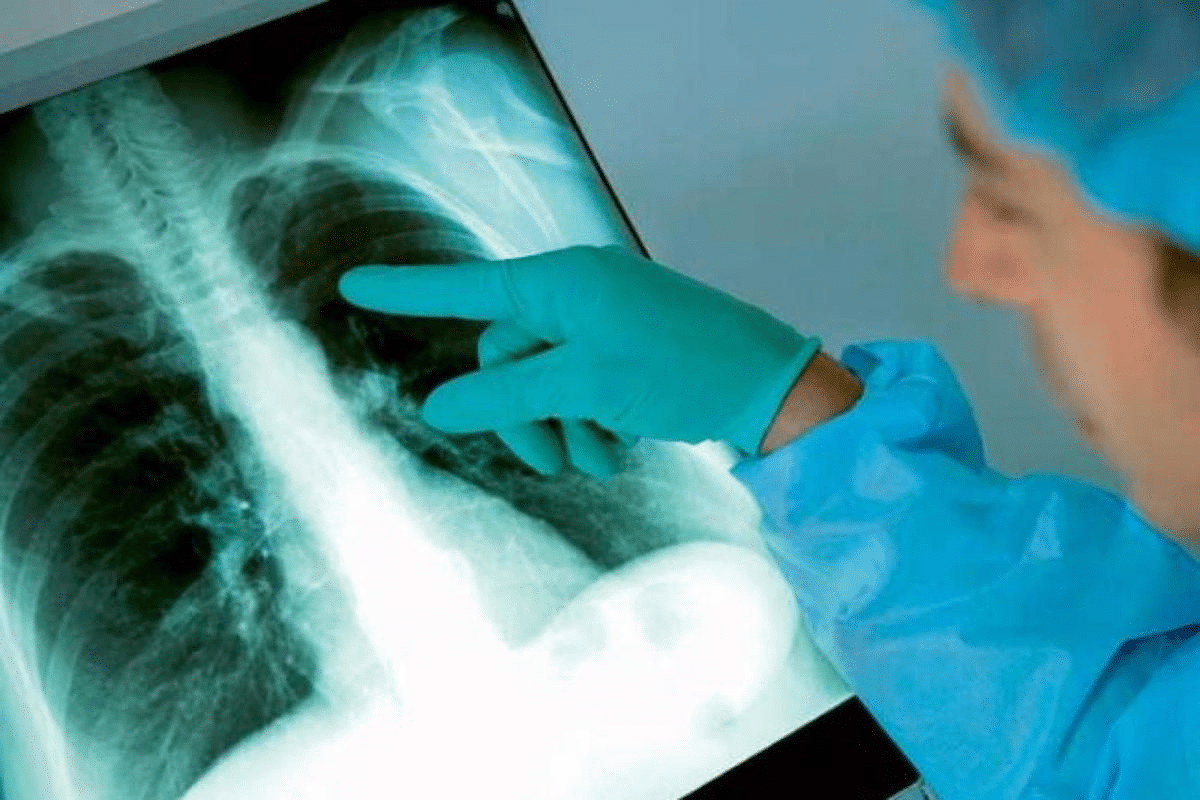

It’s important to know how a chest X-ray looks different when it shows pneumonia. At Liv Hospital, we focus on getting the right images to spot pneumonia early. This helps us treat it better.Detailed analysis showing the visual differences between pneumonia chest x ray vs normal lung fields clearly.

Pneumonia shows up as white spots on X-rays. These spots mean there’s inflammation and fluid in the lungs. On the other hand, healthy lungs look clear and sharp on X-rays. Our team uses the newest methods to spot pneumonia right away. This means we can give the right treatment fast.

Chest X-rays are key in finding lung problems and helping treat infections. They show the lungs clearly, helping doctors spot many respiratory issues, like pneumonia.

Basic Principles of Chest Radiography

Chest X-rays are a non-invasive way to see the heart, lungs, and chest wall. They work by showing how different tissues absorb X-rays, creating images. This helps doctors see lung problems, like pneumonia.

Role in Respiratory Disease Diagnosis

Chest X-rays are vital for spotting respiratory diseases. They show lung issues, like opacities and consolidation, which help diagnose pneumonia. Doctors use these signs to figure out the type of pneumonia and how to treat it.

Pneumonia Chest X-Ray vs Normal: Key Differences

It’s important to know how pneumonia and normal chest X-rays differ. We look for certain patterns and changes to tell them apart. This helps us care for patients better.

Characteristic Infiltrates and Opacities

Pneumonia shows up as dense, patchy areas on X-rays. These infiltrates and opacities are caused by fluid or pus in the lungs. They make the lung look whiter than usual.

It’s important to know how pneumonia and normal lung tissue look on chest X-rays. Chest X-rays help doctors find and understand pneumonia. They show how bad the infection is.

Pneumonia chest X-rays show different things than normal ones. Pneumonia has infiltrates and opacities that a normal X-ray doesn’t. Doctors need to know these differences to make good choices.

An X-ray with pneumonia often has consolidation or ground-glass opacities. These signs mean there’s an infection. Knowing how to spot these helps doctors track the disease.

Chest X-rays are key in fighting pneumonia. By reading these images right, doctors can start treatment fast. This helps patients get better sooner.